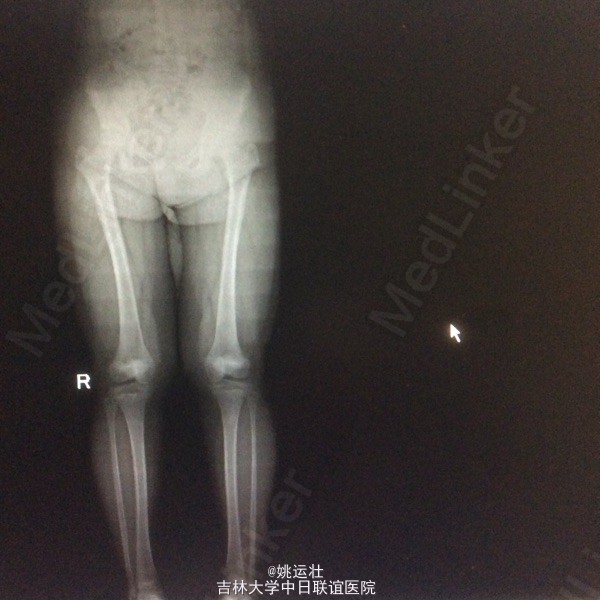

胸椎半椎体畸形 左侧第10肋骨缺如 隐形骶椎裂 双下肢膝外翻 双下肢肌挛缩症 脊柱畸形术,胸5、6、8、9腰1-2-3双侧椎弓根螺钉,去除胸11-12后方椎板,胸12半椎体及上下间隙间盘去除,椎间隙植骨。